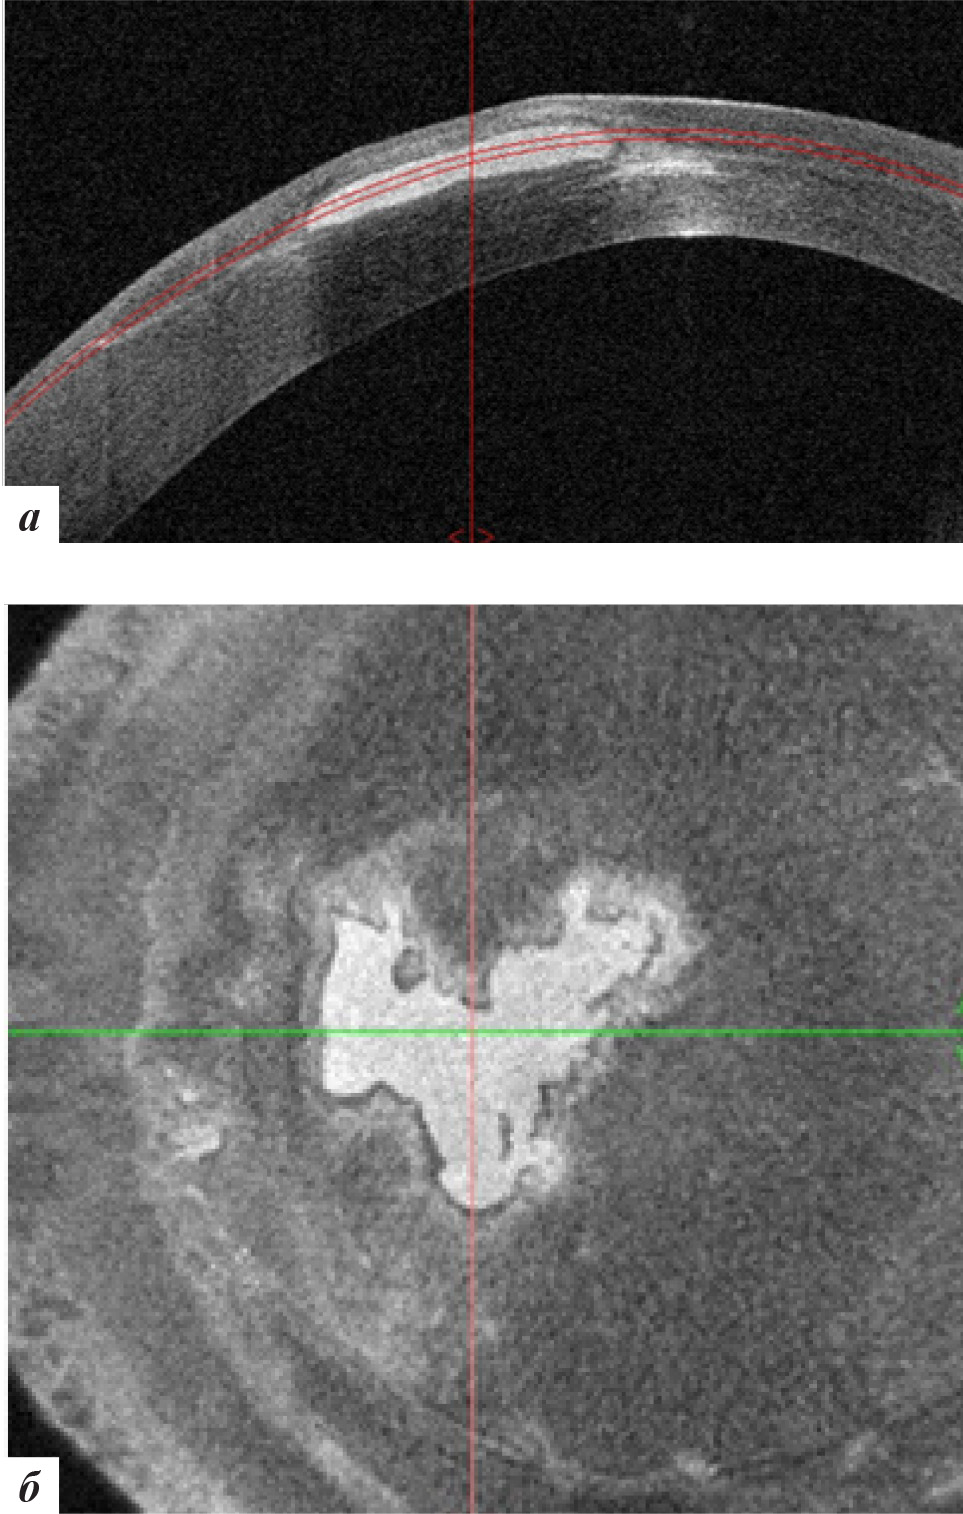

Рис. 2. Данные ОКТ роговицы правого глаза: а – горизонтальная проекция; б – фронтальная проекция

Рис. 4. Данные ОКТ роговицы левого глаза: а – горизонтальная проекция, б – фронтальная проекция